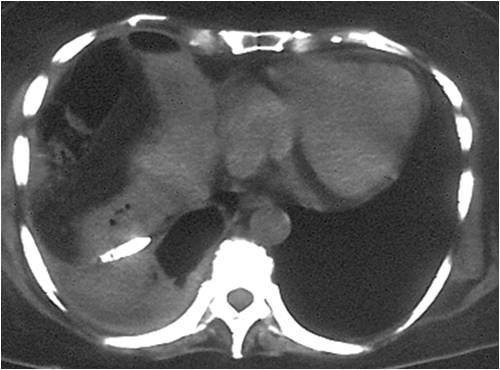

- Right sub diaphragmatic abscess post right hemicolectomy

- Successful drainage